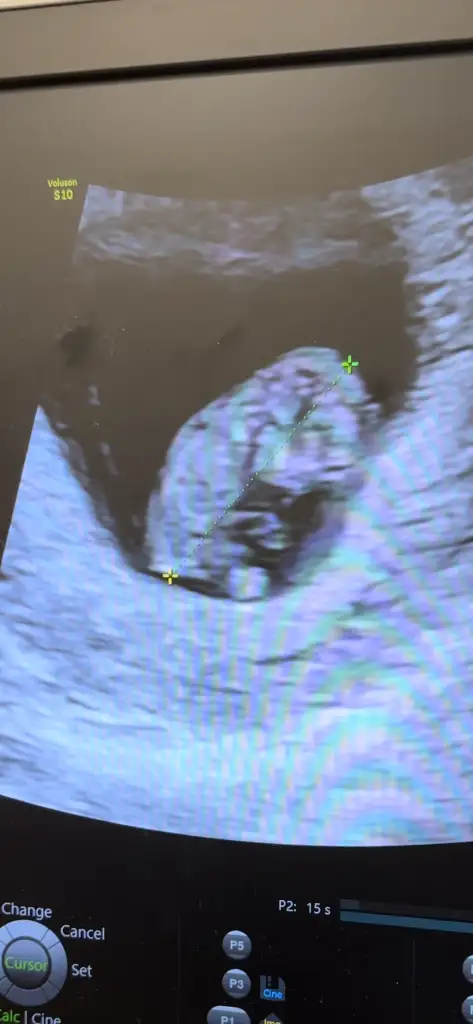

Kızlar merhaba 13+6 nubu kız gibi ama bacak arasından dolayı emin olamadım siz ne düşünüyorsunuz